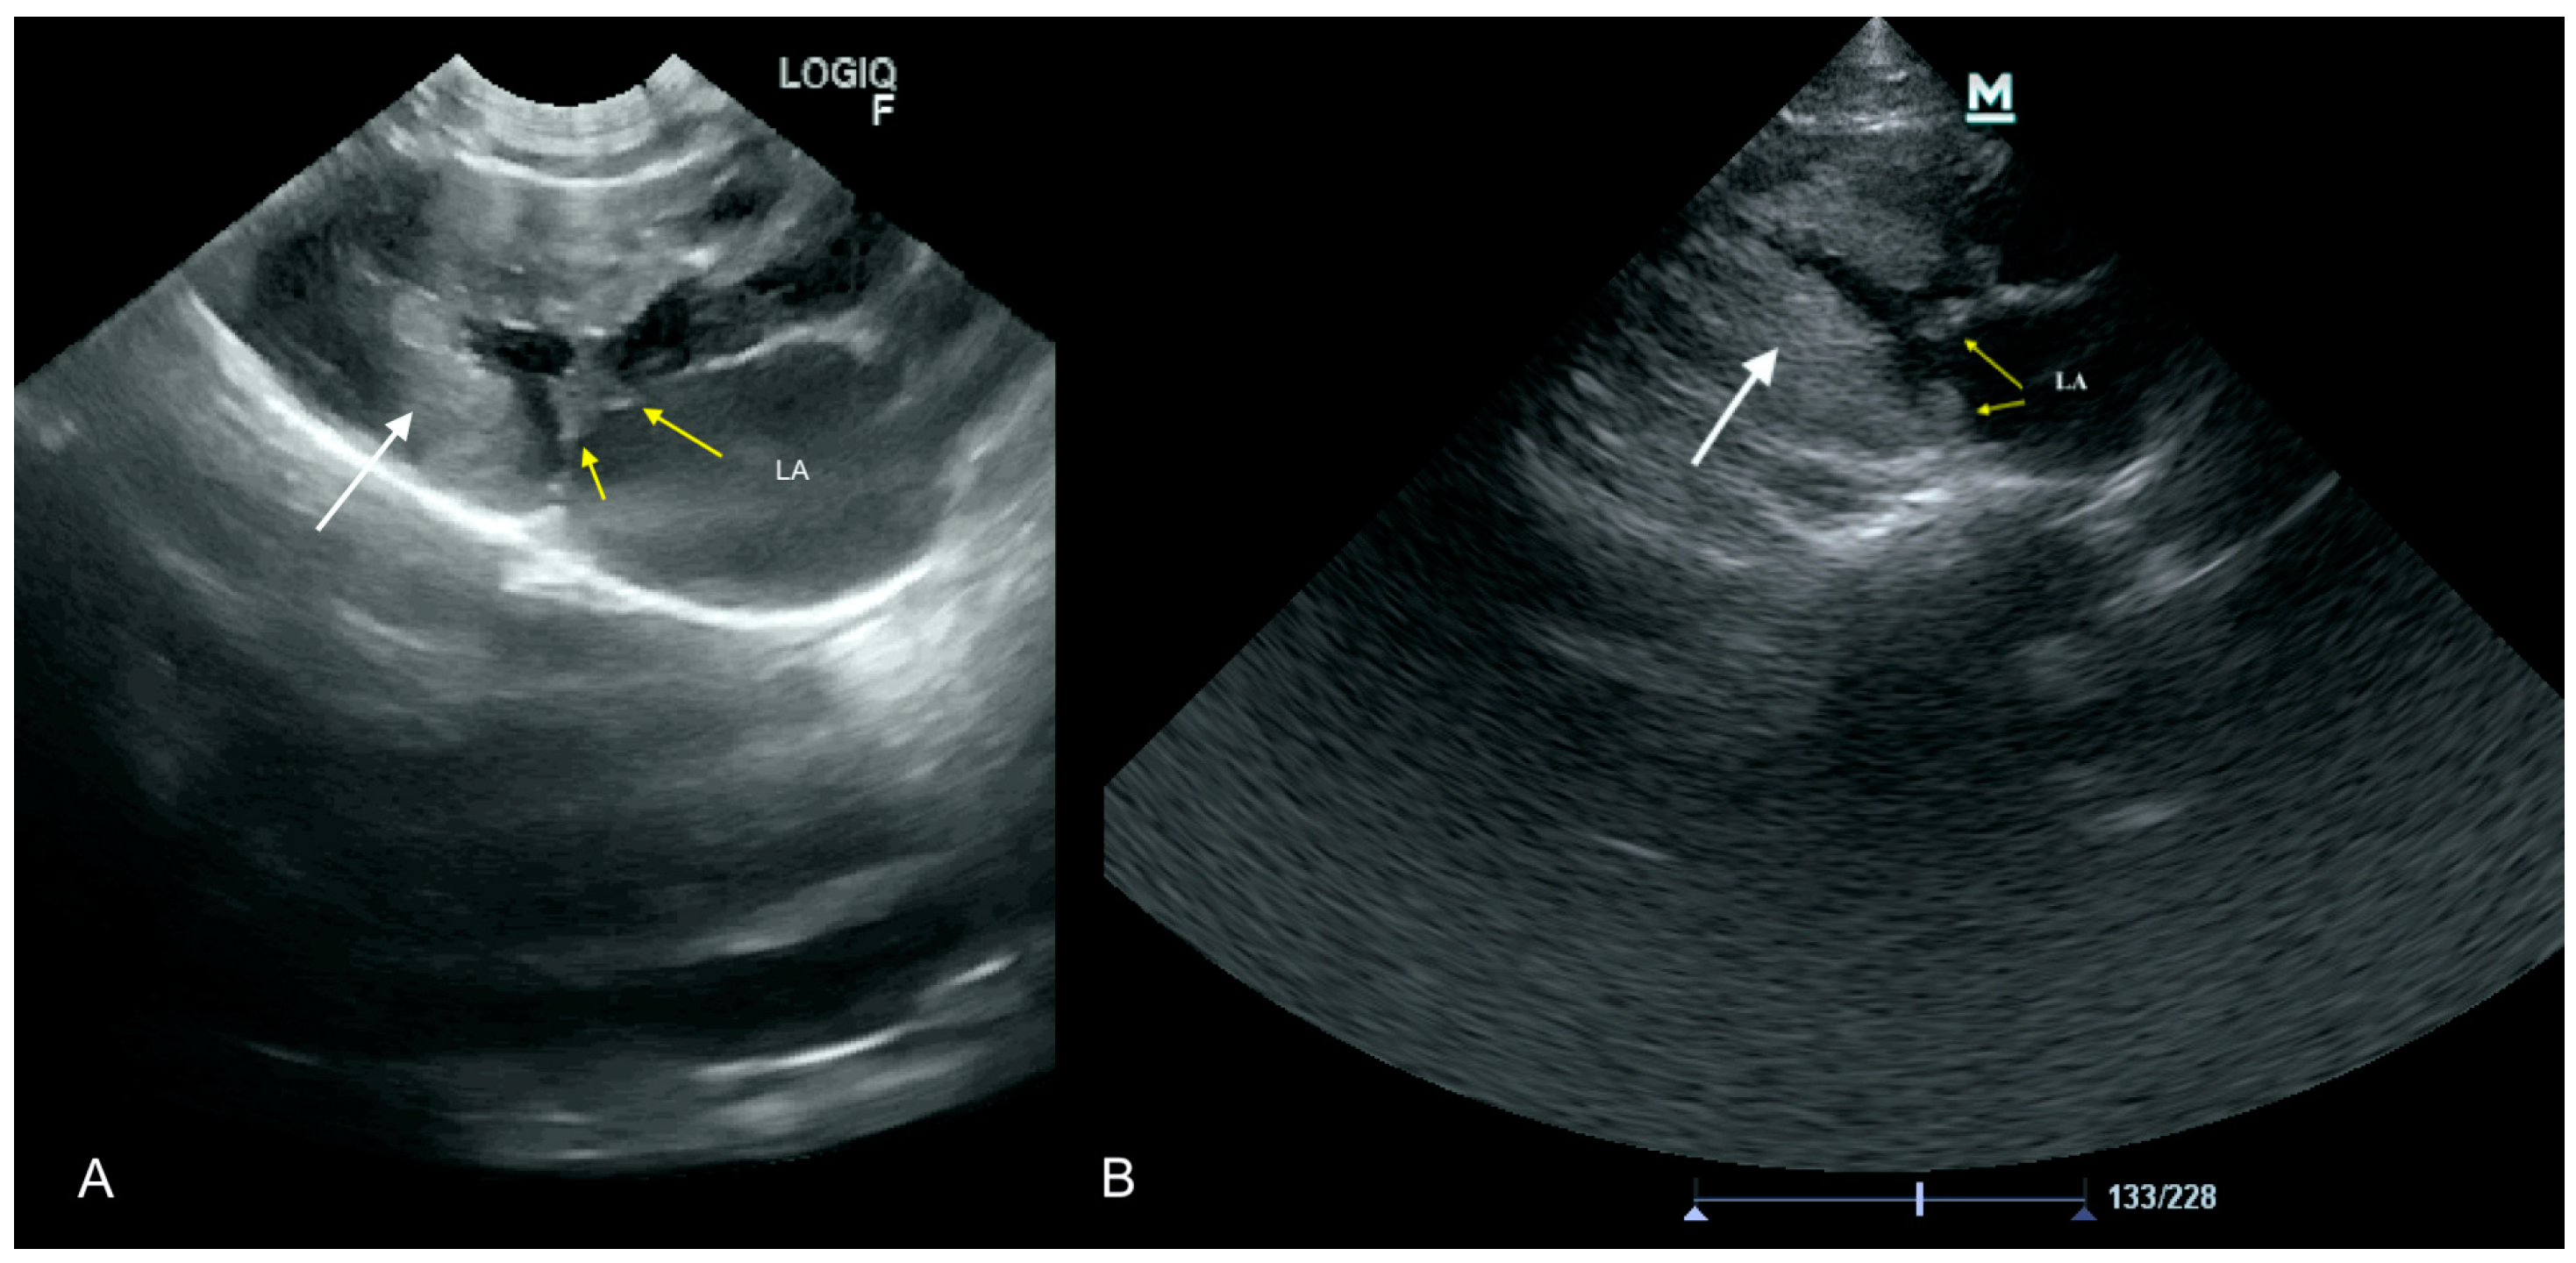

3.3. Case No. 3

3.4. Case No. 4